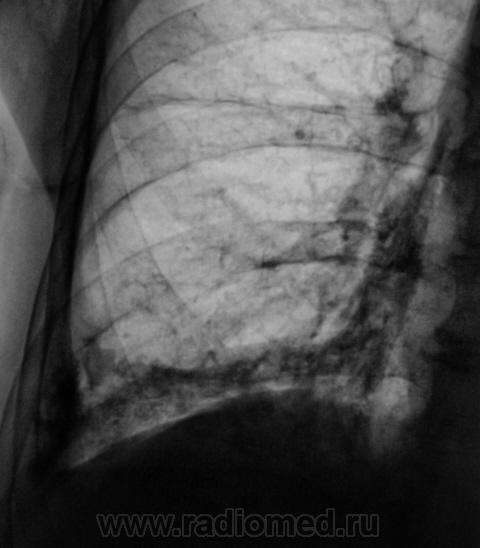

Пациент направлен на рентгенографию ОГК.

А томограмм нет. Просто демонстируется обызвествленная плевра.